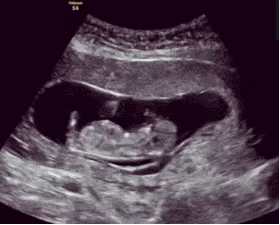

胎儿是很聪明的,一般从怀孕四个月起,胎儿就有了敏感的听觉,所以孕中期可以开始做胎教,刺激胎儿的听觉神经发育。

胎儿的听觉系统在孕期就已经发育,胎儿在孕六个月的时候,能听到外界的声音,包括妈妈的说话声,呼吸声。所以,孕期做胎教还是很有必要的,而且胎儿能感觉到,但并不一定能完全理解胎教中的全部意思。

我是二胎妈妈,孕期6个月的时候就明显感觉到胎宝宝对声音很敏感。每次播放胎教音乐的时候,胎儿就会随着音乐动起来,可以感觉到宝宝很兴奋。原来,4个月的时候胎儿听觉器官已初步发育完全,但对接收外界声音还是比较模糊,但到了第6 个月时,胎宝宝的听力就与成人无异了,真的是神奇。

听觉胎教,也就是给胎儿播放一些贝多芬的音乐、读读故事书等。但其实这些声音到达羊水中的宝宝,只是一阵噪音而已。